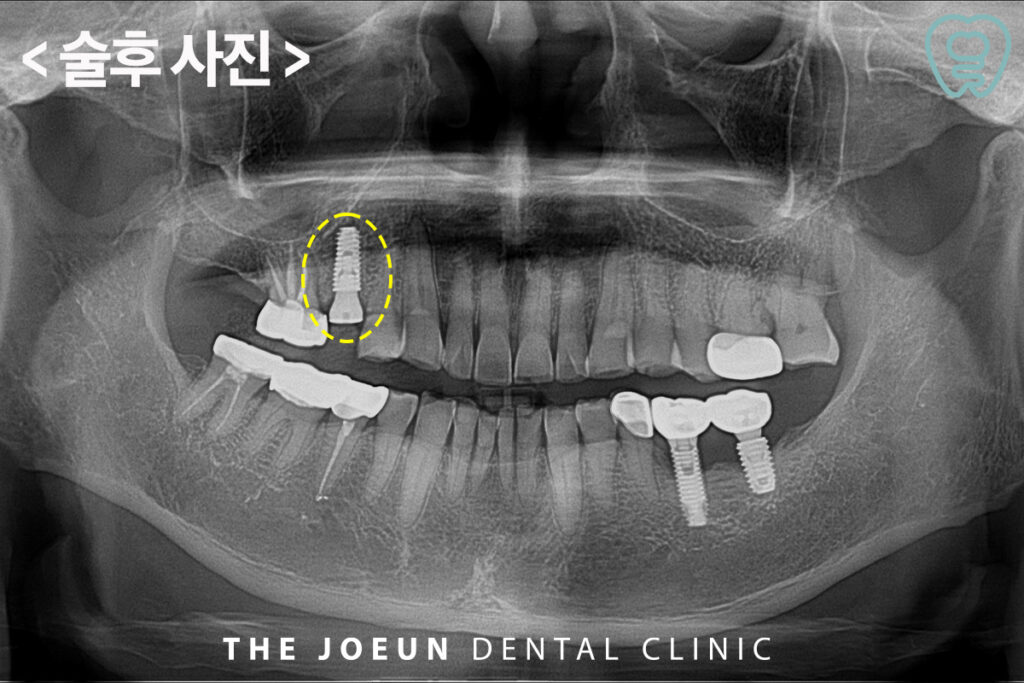

이미 치아가 부서져 조각조각 말끔히 발치를 한 후, 바로 임플란트 식립을 진행하였는데요. 식립에 앞서 반드시 정밀 치과 진단을 통해 구강 상태를 확인하고 정석적인 치료 계획을 세울 수 있어야 합니다. 이 과정에서 CT 촬영과 구강 스캐너를 활용해 신경과 혈관 등 주변 조직의 위치, 치아와 잇몸뼈의 상태에 대한 데이터를 활용하는 것이 중요합니다.